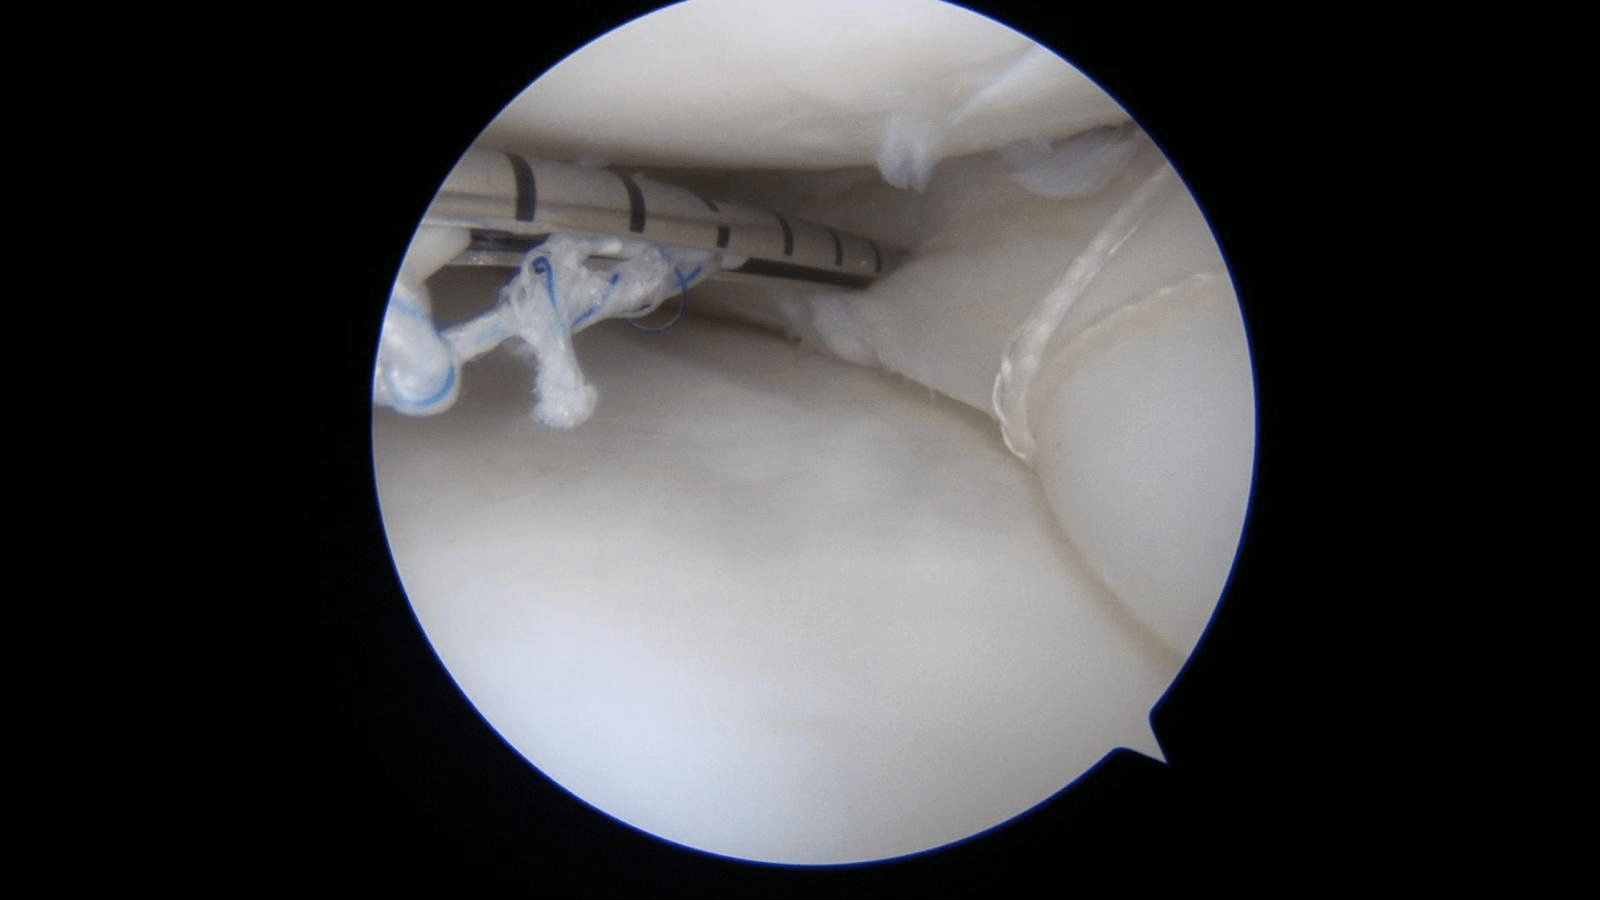

Chirurgia meniscului prin sutură

Sutura meniscală este prima soluție recomandată în cazul rupturilor de menisc și vizează păstrarea in intregime a acestuia pe termen lung. Sutura de menisc este indicată în special în cazul pacientilor tineri. Rata de succes a suturii meniscale depinde de regiunea meniscala unde este necesara, tehnica chirurgicala folosita si de programul de recuperare postoperator

Rupturile de menisc periferice din zona roșie vascularizată au șanse de vindecare mai mari decât cele din zona albă nevascularizată. Beneficiile procedurii artroscopice oferă precizie în diagnosticare și în efectuarea suturilor, cu reducerea durerii postoperatorii. Recuperarea după sutura de menisc este mai lentă față de cea după meniscectomie, cu restricții de mobilitate a articulatiei genunchiului in primele saptamani postoperator.